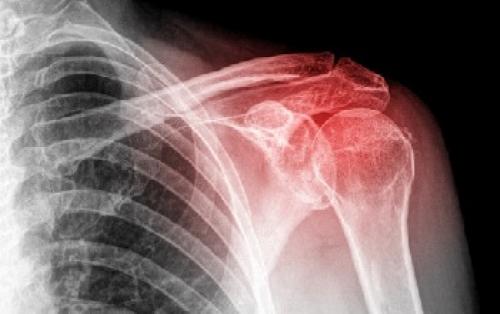

Для точной диагностики артрита плечевого сустава используют методы рентгенографии и компьютерной томографии.